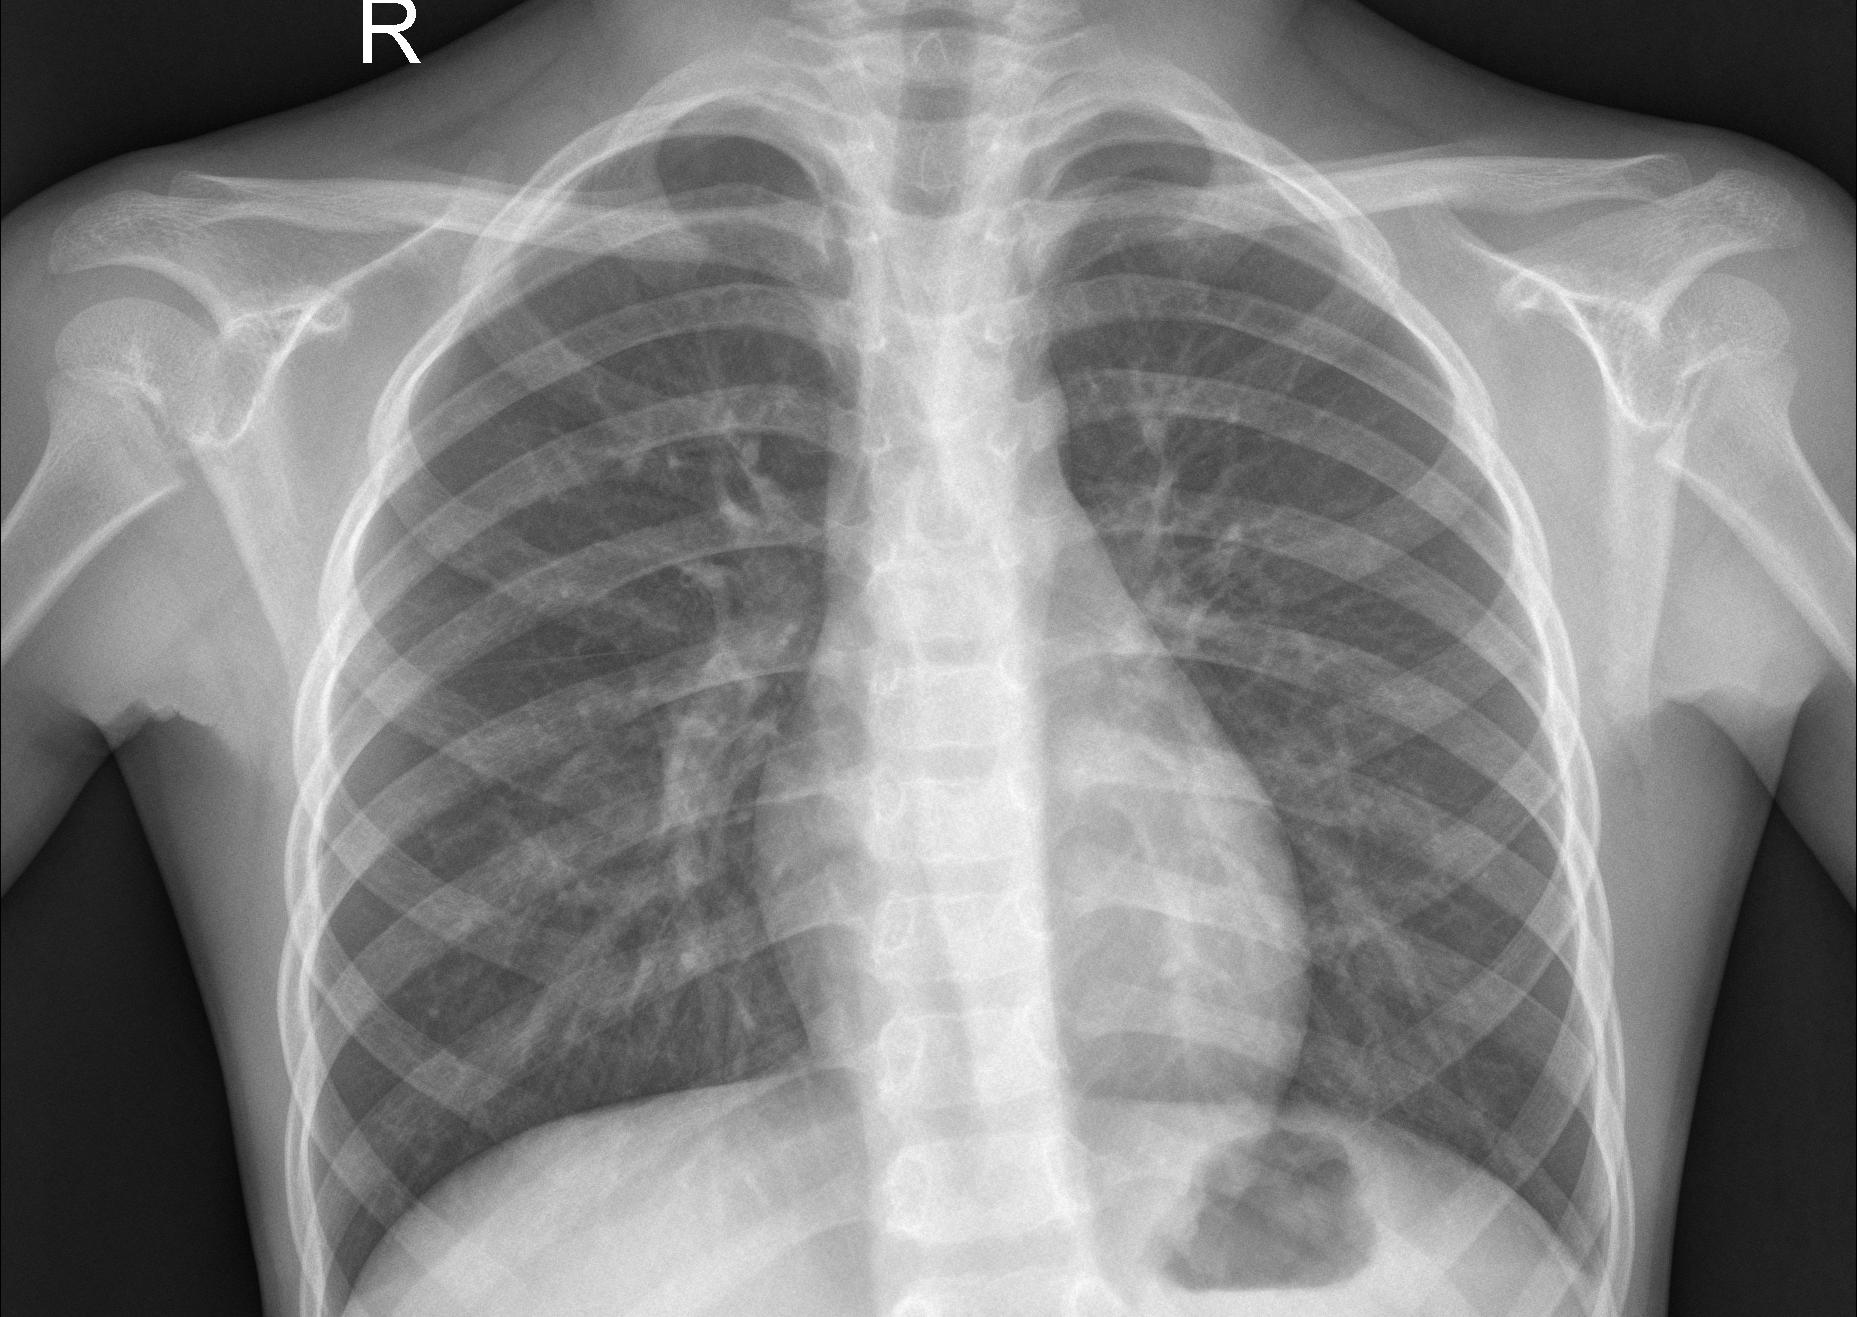

We conduct human subject experiments on two image classification datasets: a natural image dataset, Butterflies v.s. Moths (BM) and a medical image dataset of chest X-rays (CXR). For BM, we followed Singla et al. (2014) and acquired 200 images from ImageNet Krizhevsky et al. (2012). BM is a binary classification problem and each class contains two species. CXR is a balanced binary classification subset taken from Kermany et al. (2018) with 3,166 chest X-ray images that are labeled with either normal or pneumonia. We randomly split the datasets following 60%:20%:20% ratio. The classification accuracy with our base supervised learning models are 97.5% for BM and 97.3% for CXR. We only present results with human subjects in the main paper, but results from simulation experiments with TML as a synthetic agent, such as filtering triplets providing better results, are qualitatively consistent. See §D and §E in the appendix for more details.

Refer to caption

(b) Pneumonia classification.

Figure 4: Decision support accuracy with human subject studies. Error bars show 95% confidence intervals. HC dominates MLE in both neutral and persuasive decision support.

Decision support results show HC is significantly better than MLE both in neutral and persuasive decision support. Combining two example selection policies with two representations, we have four conditions: HC neutral, HC persuasive, MLE neutral, MLE persuasive. We also add a baseline condition with random supporting examples, which we call random in-class random out-of-class (RIRO). We recruit 30 Prolific workers for each condition and ask them to go through the images in the test set with supporting examples from each class in the training set. Both the order of the test images and the order of the supporting images within each test question are randomly shuffled.

Figure 4(a) shows the human classification accuracies with different decision support scenarios and different representations. In neutral decision support, we observe that HC achieves much higher accuracy than MLE (95.3% vs. 60.5%, p=4e19𝑝4e19p=4\mathrm{e}{-19} with two-sample t-test). In fact, even RIRO provides better decision support than MLE representations, suggesting that the supporting images based on MLE are confusing and hurt human decision making (77.5% vs. 60.5%, p=3e6𝑝3e6p=3\mathrm{e}{-6}). As expected, the accuracies are generally higher in persuasive decision support. HC enables an accuracy of 97.8%, which is much better than MLE at 79.5% (p=2e13𝑝2e13p=2\mathrm{e}{-13}). HC in neutral decision support already outperforms MLE in persuasive decision support. These findings confirm our results with VW synthetic experiments that human-compatible representations provide much better decision support than MLE representations.

5.3 Results on Chest X-rays

We use the same experimental setup as BM to evaluate HC and MLE representations in CXR.

H2H comparison results show HC NI examples are slightly preferred over MLE NI examples but the difference is not statistically significant. We recruit 50 Prolific workers to each make 20 H2H comparisons between HC NI examples and MLE NI examples. The mean preference for HC over MLE is 0.516 with a 95% confidence interval of ±0.0725plus-or-minus0.0725\pm 0.0725 (p=0.379𝑝0.379p=0.379 with one-sample t-test). H2H comparison in CXR is especially challenging as laypeople need to differentiate between two chest X-rays in the same class, hence the slightly worse performance in H2H compared to BM.

Similar to BM, HC outperforms MLE in both neutral and persuasive decision support in CXR. As expected, Fig. 4(b) shows that pneumonia classification is a much harder task than butterfly vs. moth classification, indicated by the lower accuracies across all conditions. In neutral decision support, HC enables much better accuracy than MLE (79.1% vs. 63.8%, p=2e8𝑝2e8p=2\mathrm{e}{-8} with two-sample t-test). In fact, similar to the BM setting, MLE provides similar performance with RIRO (63.8% vs. 65.9%, p=0.390𝑝0.390p=0.390), suggesting that MLE representations are no different from random representations for selecting nearest neighbors within a class. To contextualize our results, we would like to highlight that our crowdworkers are laypeople and have no medical training. It is thus impressive that human-compatible representations enable an accuracy of almost 80% in neutral decision support, which demonstrates the potential of human-compatible representations.

In persuasive decision support, HC provides the highest decision support accuracy at 90.0%, also much higher than MLE at 77.0% (p=2e10𝑝2e10p=2\mathrm{e}{-10}). Again, while we do not recommend persuasive decision support as a policy for decision support in practice, these results show that our human-compatible representations are indeed more compatible with humans than MLE representations.